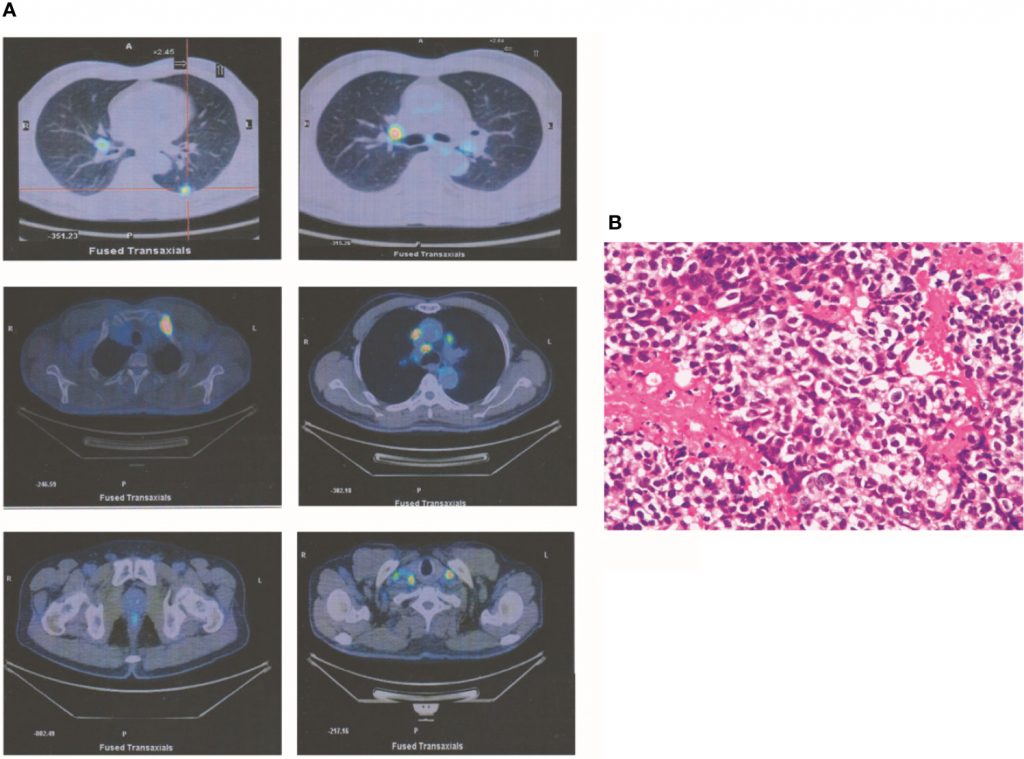

一名67岁男性有超过20年的吸烟史,每天吸烟20支,尽管他在就诊前10年戒烟。2015年7月,因右侧锁骨上淋巴结肿大就诊。体格检查发现右侧锁骨上淋巴结肿大,不痛。实验室数据正常,不包括癌胚抗原(CEA)水平升高(8.7)。正电子发射断层扫描(PET)显示左肺1个占位性病变,以及右锁骨上淋巴结肿大和多发纵隔淋巴结肿大。此外,有多处骨转移,包括第四颈椎、左第一肋骨和左耻骨转移(图1A))。根据第八版肺癌分类,这种恶性肿瘤的分期为IV期(T1cN3M1b)。在右侧锁骨上淋巴结肿大部位行经皮穿刺活检。根据免疫组化分析结果,诊断为低分化腺癌(图1B)。通过新一代测序(NGS)和原位荧光杂交,在活检样本中检测到ALKr。因此开始克唑替尼治疗,3个月后所有病灶缩小。此外,此时CEA水平已降至6.7。随访结束时,除左肺病灶外,所有病灶均进一步缩小,情况稳定。实验室分析显示CEA水平正常(<5.0)。

图1

图1一名T1cN3M1bNSCLC患者。(A) PET显示左肺有一个占位性病变。右侧锁骨上淋巴结肿大1处,纵隔多发淋巴结肿大。此外,还有多处骨转移,包括第四颈椎、左侧第一肋骨和左侧耻骨。(B)根据免疫组化分析,诊断为低分化腺癌。